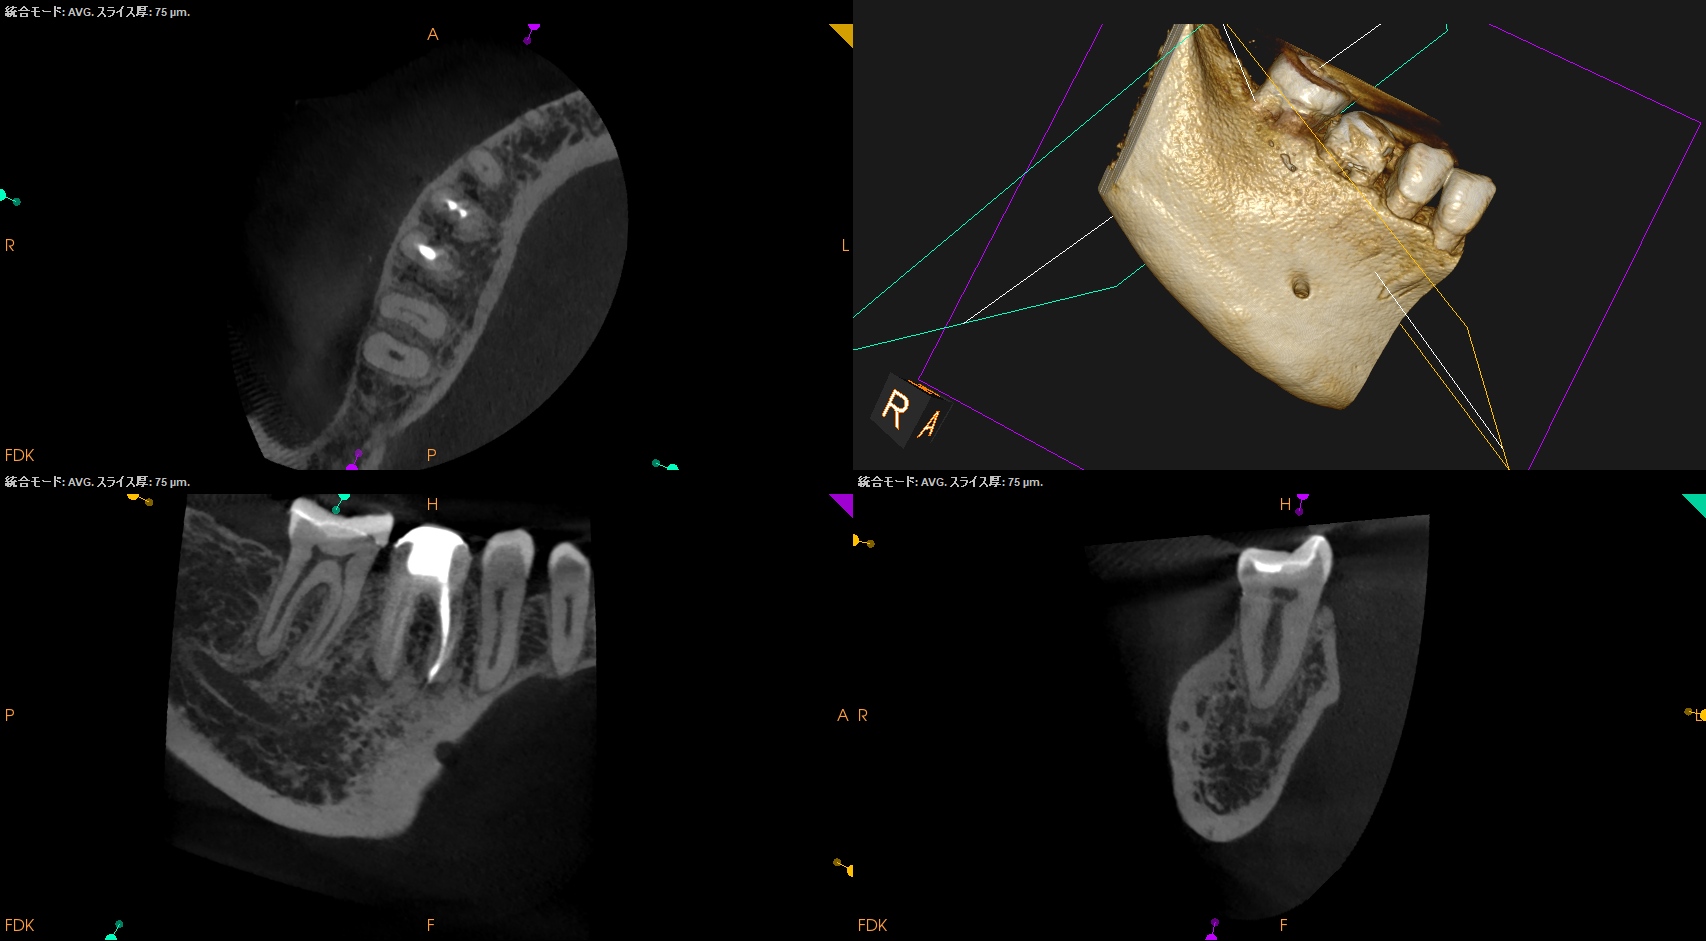

CBCT(2025.8.29)

#30

MB

ML

D

#31

MBとML,どちらがストレートか?と言えばMLの方だろう。

MLをメイン根管にしてMBはそこに合流するという風に形成・根充すべきだろう。